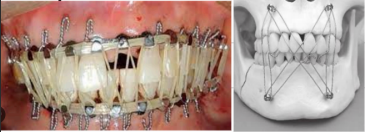

Tratamiento de las fracturas maxilares

A

Fijación intermaxilar